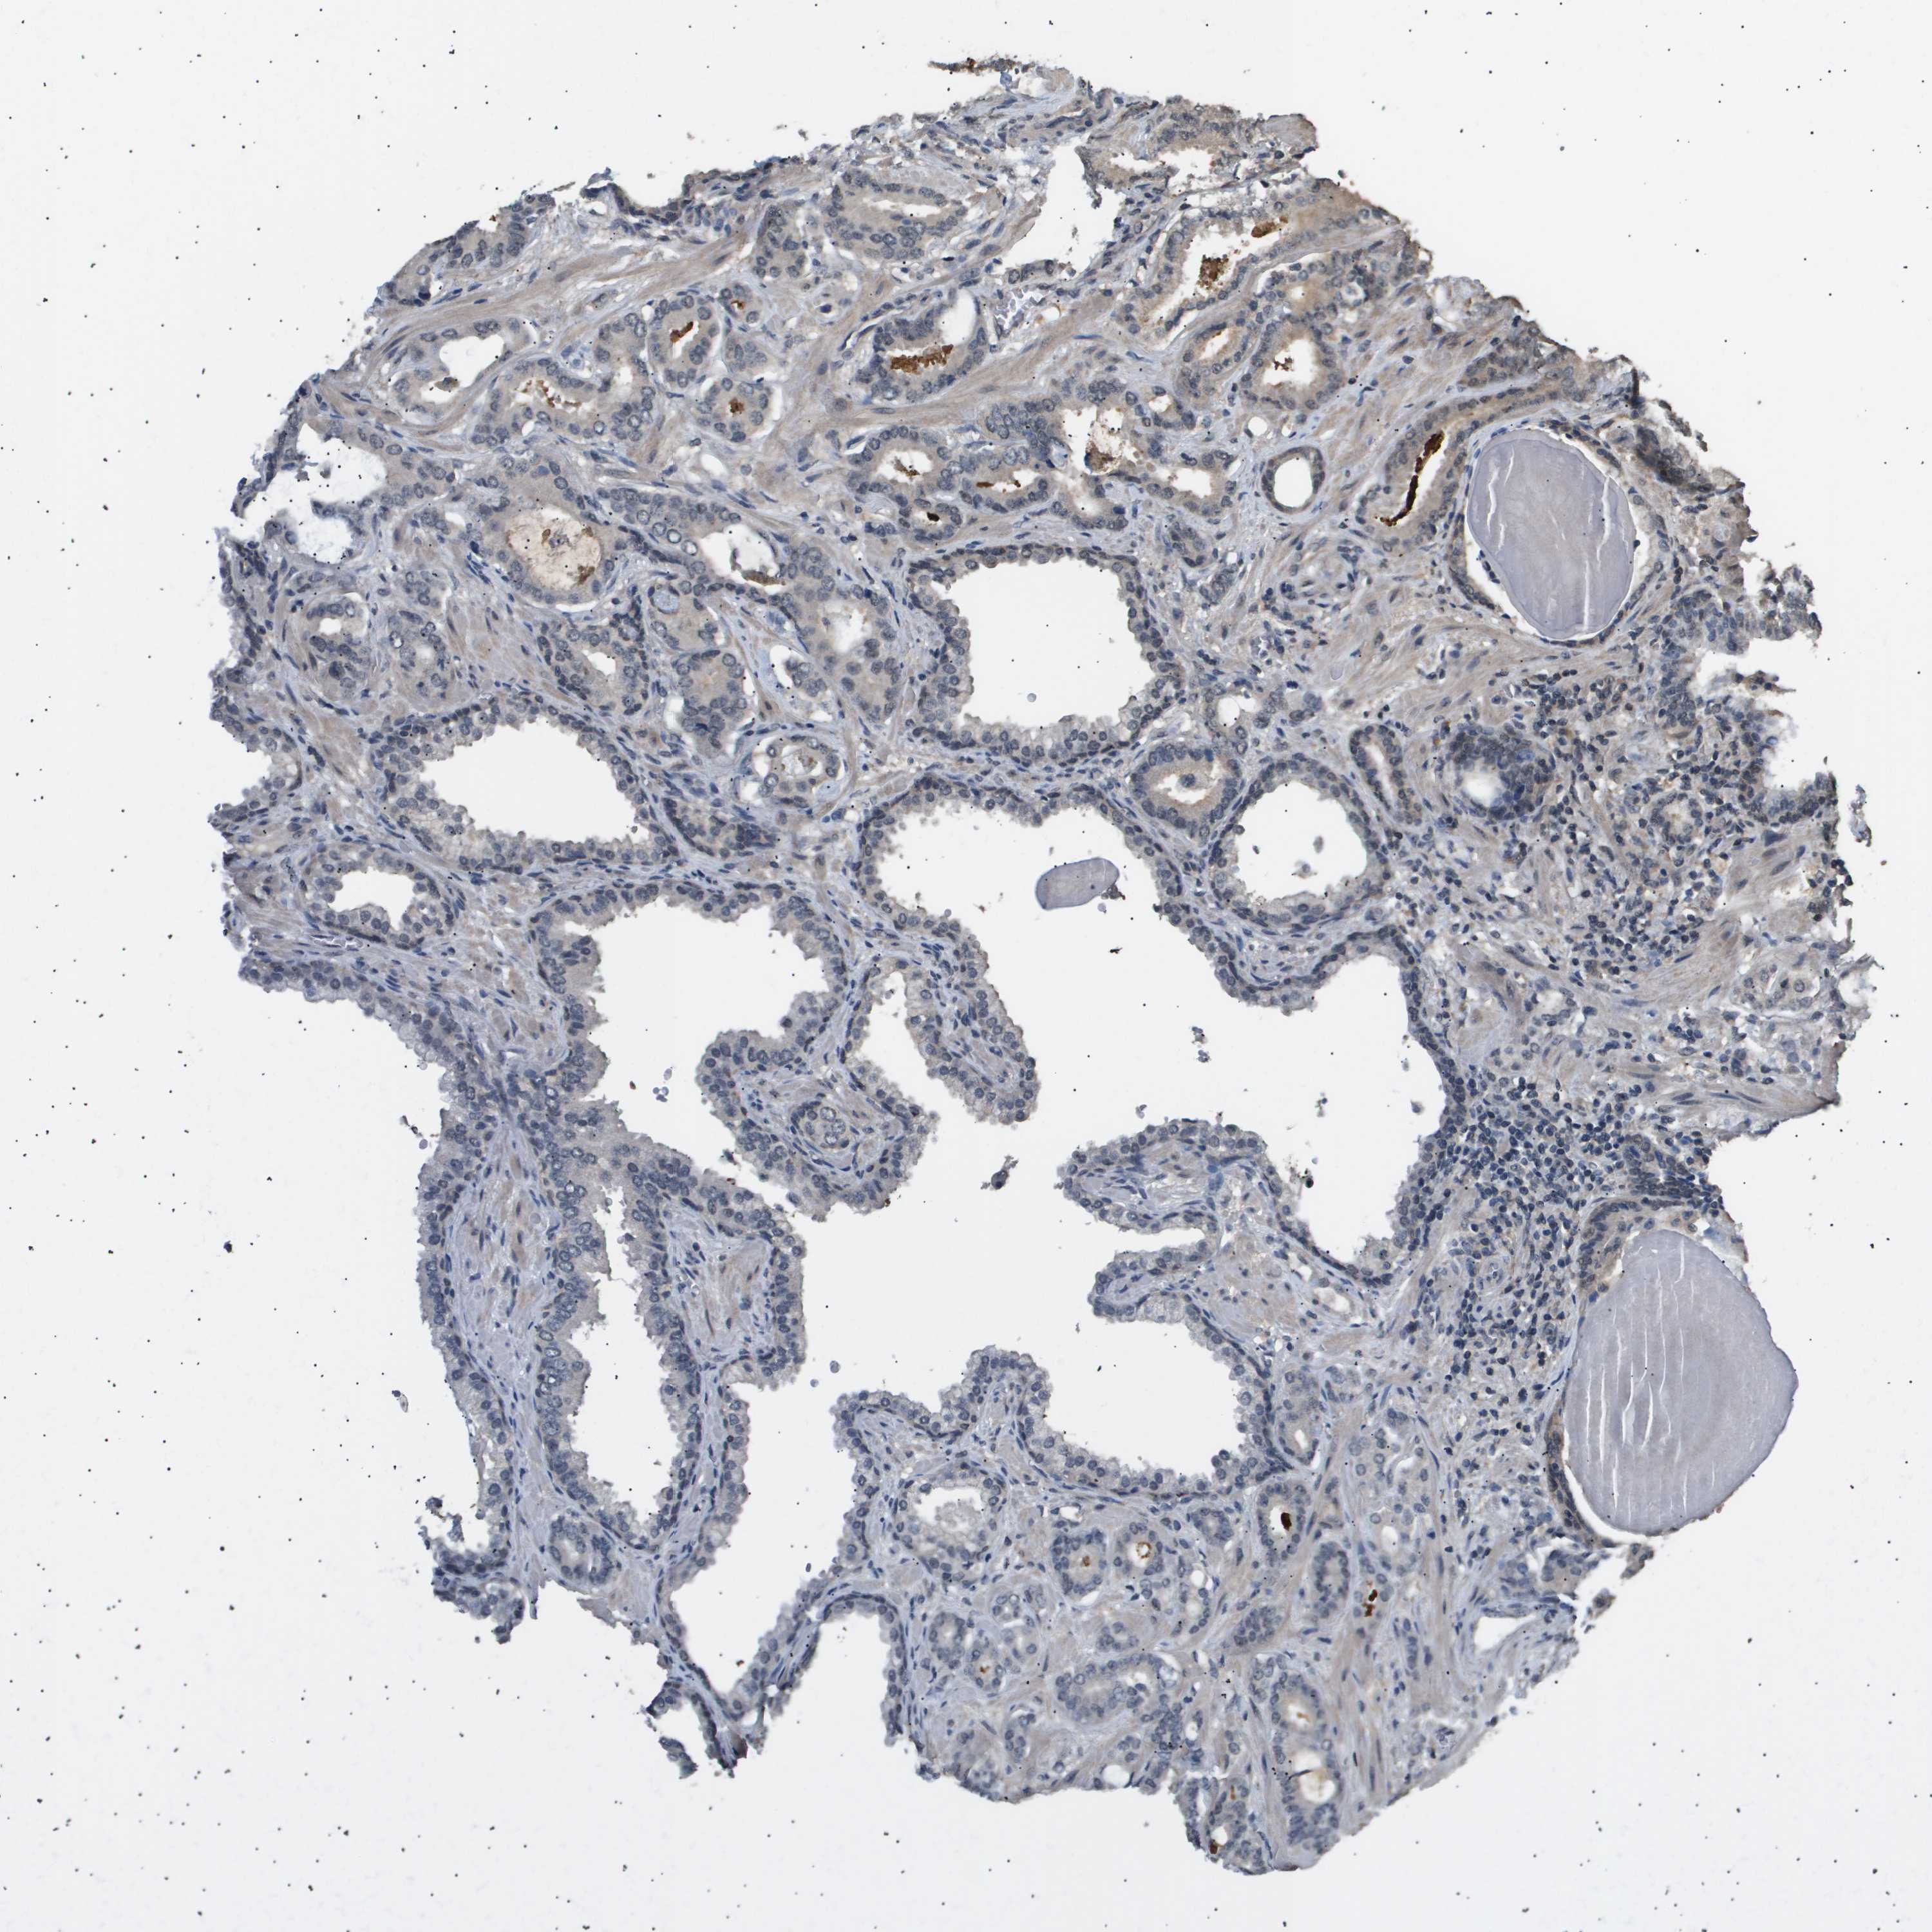

PROSTATE CANCER - Protein expressioni

A mouse-over function shows sample information and annotation data. Click on an image to view it in a full screen mode. Samples can be filtered based on level of antibody staining by selecting one or several of the following categories: high, medium, low and not detected. The assay and annotation is described here.

Antibody stainingi

Antibody staining in the annotated cell types in the current human tissue is reported as not detected, low, medium, or high, based on conventional immunohistochemistry profiling in selected tissues. This score is based on the combination of the staining intensity and fraction of stained cells.

Each image is clickable and will lead to virtual microscopy that enables deeper exploration of all samples and also displays staining intensity scores, fraction scores and subcellular localization as well as patient and tissue information for each sample.

Antibody CAB016136

Antibody CAB017773

Staining

High

Medium

Low

Not detected

Intensity

Strong

Moderate

Weak

Negative

Quantity

>75%

75%-25%

<25%

None

Location

Nuclear

Cytoplasmic/membranous

Cytoplasmic/membranous,nuclear

Adenocarcinoma, Low grade

Adenocarcinoma, High grade